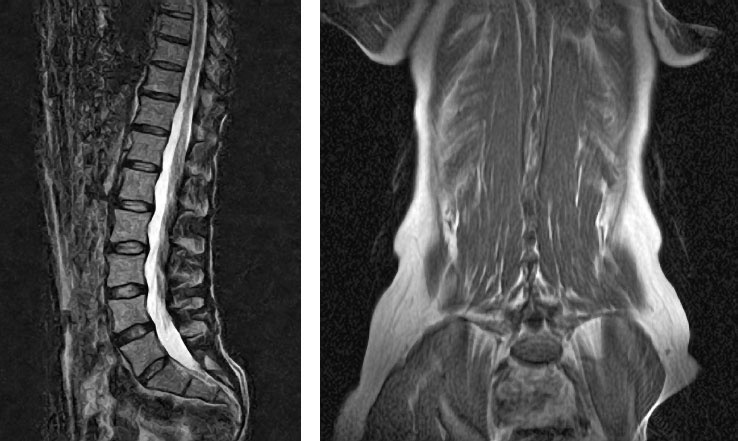

Иллюстрация к книге — Йога при остеопорозе [_18.jpg]

Рисунок 15. Нагрузка способствует повышению плотности кости. Йога компенсирует ущерб, причиненный повседневной деятельностью. Обратите внимание на прекрасный позвоночник этого практика и учителя йоги с 16-летним стажем.